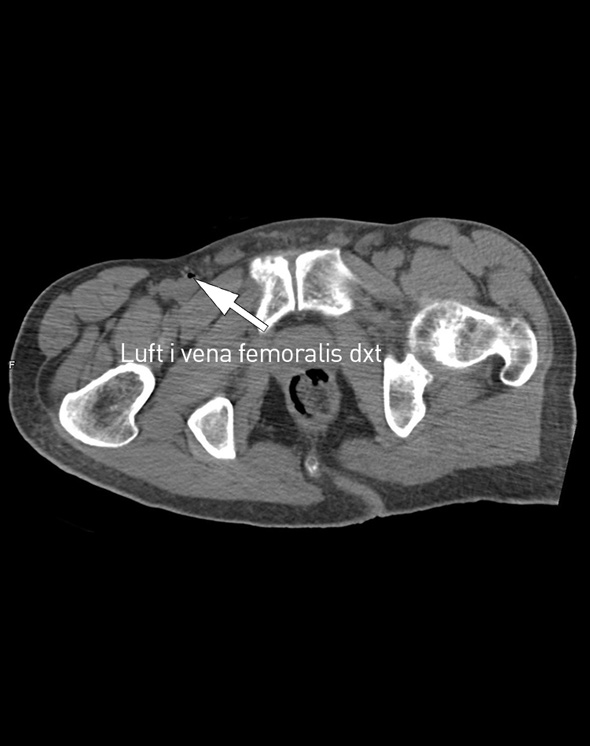

På sykehuset fikk han flere venekanyler i overekstremitetene. Den intraossøse nålen ble fjernet etter å ha vært åpen rundt en halvtime mens pasienten lå i sjokkleie. CT-undersøkelse av thorax, abdomen og bekken uten intravenøs kontrast tatt kort tid etter ankomst viste luft i høyre vena femoralis, vena cava inferior og venstre nyrevene. Sikker årsak til hjertestans ble ikke funnet, og pasienten døde etter et kort intensivopphold.